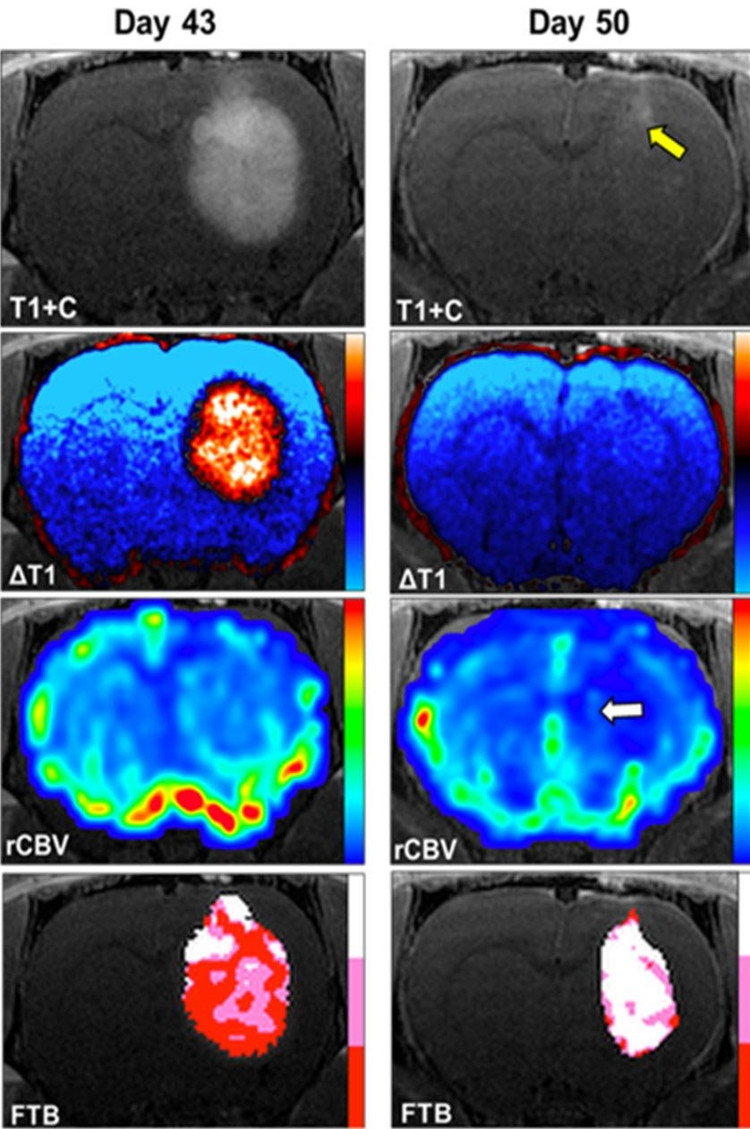

Trong các nghiên cứu tiền lâm sàng, TS Chitambar và TS Kathleen Schmainda đã phát hiện, khi tiêm tĩnh mạch, gali maltolate (GaM) làm chậm đáng kể sự phát triển của u nguyên bào đệm trong mô hình khối u não chuột. Những nghiên cứu tiếp theo cho thấy, GaM điều trị qua đường uống cho chuột, mang u nguyên bào thần kinh đệm, làm giảm đáng kể kích thước khối u và kéo dài thời gian sống sót.

Chụp cộng hưởng từ (MRI) nâng cao cho thấy, một con chuột mang u nguyên bào thần kinh đệm giảm 93% thể tích khối u khi được điều trị bằng GaM.